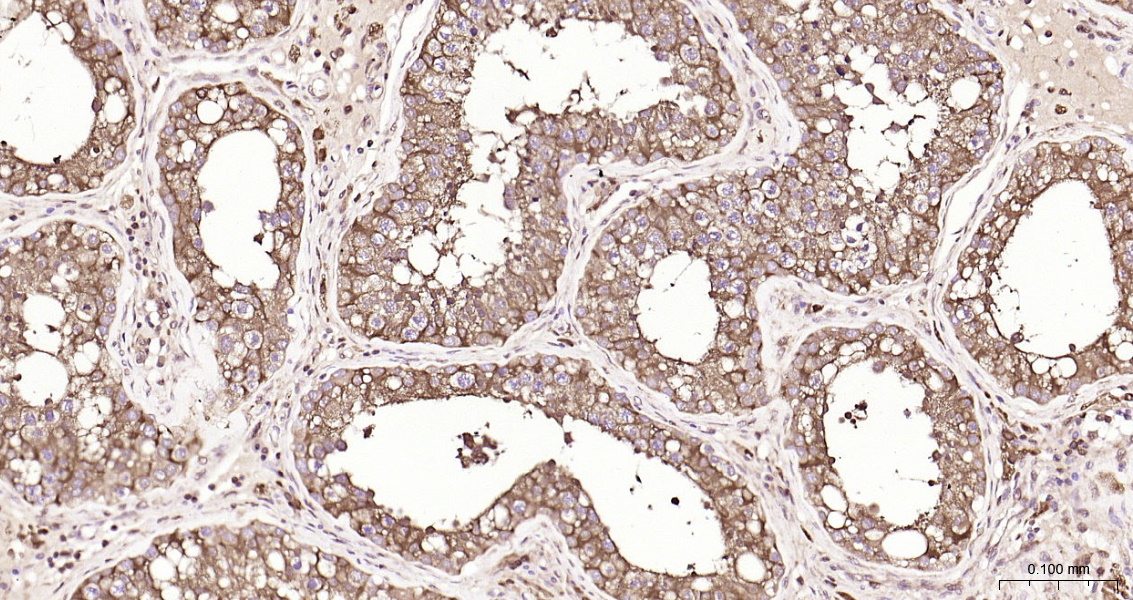

• IHC-P

IHC-P IHC-P1:50-200

IF(IHC-P) IFIHC-P1:50-200